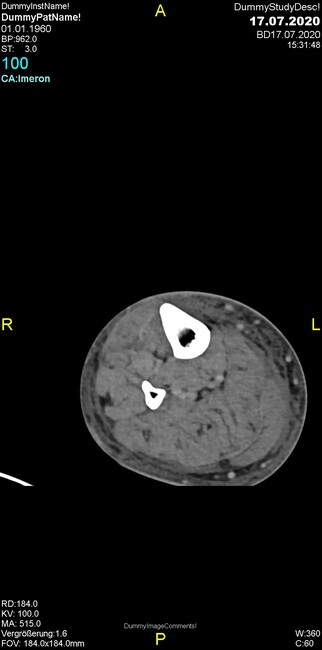

Um welche Modalitäten handelt es sich?

- Röntgen p.a. und lateral, CT coronar Knochenfenster, CT axial Weichgewebsfenster

- Röntgen p.a. und oblique, CT coronar Knochenfenster, CT axial Weichgewebsfenster

- Röntgen p.a. und lateral, CT sagittal Weichgewebsfenster, CT coronar Knochenfenster

- Röntgen p.a. und oblique, CT sagittal Knochenfenster, CT coronar Weichgewebsfenster

- Röntgen p.a. und lateral, CT coronar Weichgewebsfenster, MR axial

Was fällt in der CT im Knochenfenster auf?

- Mediale Gelenkspaltverschmälerung

- Dezente Erosion der fibulären Kortikalis

- Frakturspalt der lateralen Tibiametaphyse

- Weichgewebskalzifikationen lateral angrenzend an den Gelenkspalt

- Osteolyse der Tibiametaphyse unter Beteiligung der Kortikalis